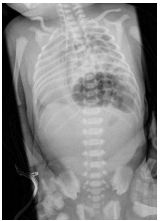

9.新生兒出生後即有呼吸窘迫、唇⾊發紫、胸部較腹部來得高突的現象。身體診察發現最大心音在右側。胸腹部 X光片如附圖,最有可能的診斷為何? (A)張力性氣胸(Tension pneumothorax) (B)食道閉鎖(Esophageal atresia) (C)十二指腸閉鎖(Duodenal atresia) (D)橫膈膜疝氣(Diaphragmatic hernia)